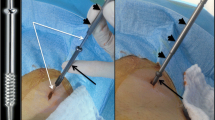

Osteolysis located in the iliac wing does not compromise the transmission of loads throughout the pelvis and prophylactic consolidation is usually not necessary [1]. However, extensive cortical and cancellous bone loss in this area may increase the risk of fracture of the iliac wing similar to that seen following bone harvesting for orthopedic and spine surgeries [51]. In particular, bone loss at the level of the anterior superior iliac spine seems to increase the risk of fracture [51, 52]. Cementoplasty is not effective to fix a pathological fracture of the iliac wing because of the complex involved stresses and the inability of cement to fix two bony fragments together [2, 23]. Percutaneous screw fixation is an excellent tool to consolidate a pathological/post-ablation iliac wing fracture, allowing early mobilization of the patient (Fig. 10) [2, 9, 53, 54]. Care should be taken to use long screws bridging the fracture line as perpendicular as possible with both extremities anchored in normal bone. The addition to cement might allow to increase the stability of the screw should the landing zone of one extremity of the screw be located in bone of poor underlying quality (e.g. osteopenia, post-radiation/ablation) [2, 9, 28].

Screw fixation of a pathological iliac wing fracture. A Axial, B coronal and C VRT CT scan show a large osteolytic metastasis with cortex destruction (white asterisk), responsible for a painful displaced fracture of the iliac wing with a mobile fragment (black asterisk). D–F Two screws were inserted perpendicular to the fracture line. Excellent immediate functional result